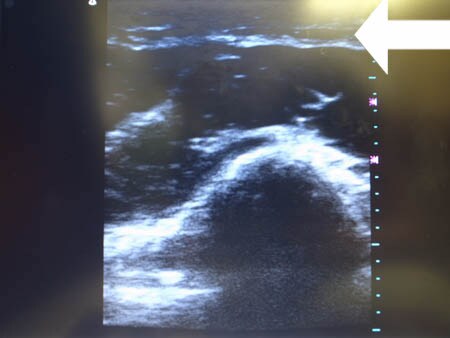

いつものように3Dタッチビュー(超音波)で

皮下脂肪層を評価してみましょう。

右二の腕

↓ ↓ ↓

上の画像の部分の皮下脂肪層をつまんでみましょう。